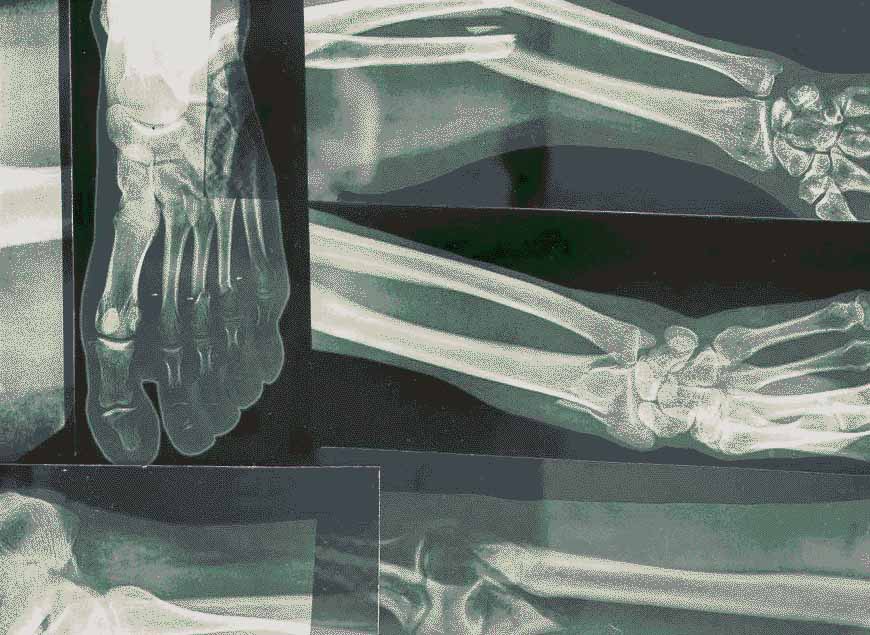

Fractures and osteoporosis represent a significant portion of the complaints that arise regarding bone health. If a bone is subjected to an impact or stress beyond its ability to withstand, it fractures. This fracture can range from a slight crack to a complete split, causing pain, swelling and impaired mobility.

Osteoporosis is a progressive disease characterised by a decrease in bone density, which can lead to increased susceptibility to fractures. As we advance in years, these conditions become not merely possibilities but rather, significant health considerations. It is important to understand that these are not inevitable ailments of old age, rather we can actively work to prevent and manage these risks through lifestyle choices, notably nutrition and physical activity. Below, we will analyse how certain nutrients can fortify the skeletal system, enhancing its resilience against these common complaints.